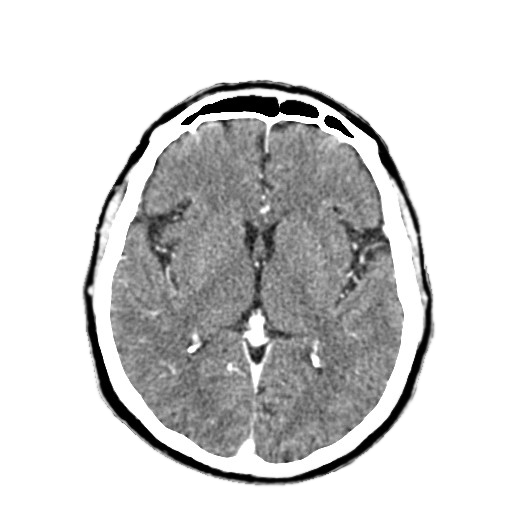

Computer tomograf constanta pret. Interpretarea se transmite in format electronic. Proceduri stricte de triaj si cele mai severe masuri de igienizare si dezinfectie. Tarife investigaţii computer tomograf ct ct craniu nativ 450 00 ct craniu nativ si cu substanta de contrast 550 00 ct denta scan 300 00 ct sinusuri 400 00 ct masiv facial inclusiv mandibula si reconstructii 3d nativ 350 00 ct masiv facial inclusiv mandibula si reconstructii 3d nativ si cu substanta de contrast 550 00 ct regiune. Poti beneficia de investigatii ct gratuit cu bilet de trimitere casmb.